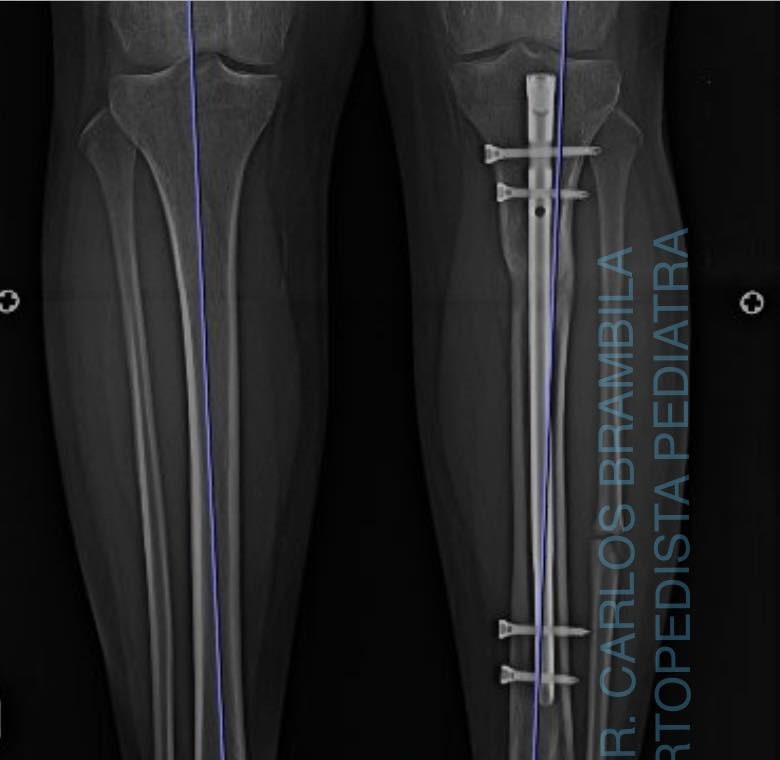

Fractura de tibia